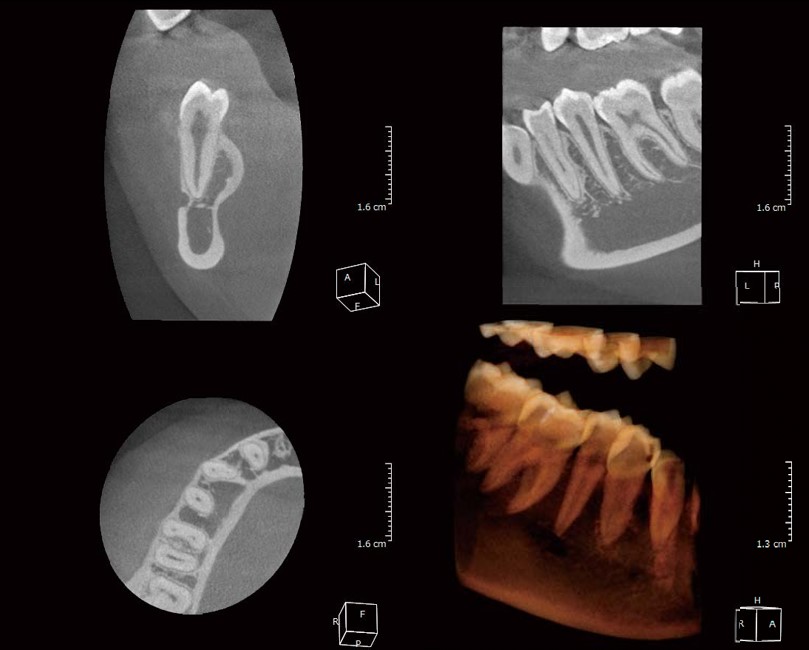

• Cung cấp hình ảnh 2D hoặc 3D (tùy thiết bị) mang đến cho Bác Sĩ cái nhìn trực quan, rõ ràng.

• Thấu kính có thể phóng đại kích thước vật thể lên nhiều lần giúp phát hiện lâm sàng các bộ phận như ống tủy, chân răng…

Thiết kế nhỏ gọn và mỏng nhưng đầy đủ chức năng, X-ERA Smart là trợ thủ tốt nhất giúp Bác Sĩ quan sát được mô hình hình ảnh toàn cảnh/cephalometric 2D, 3D.

Hình ảnh chụp toàn hàm từ X-ERA Smart